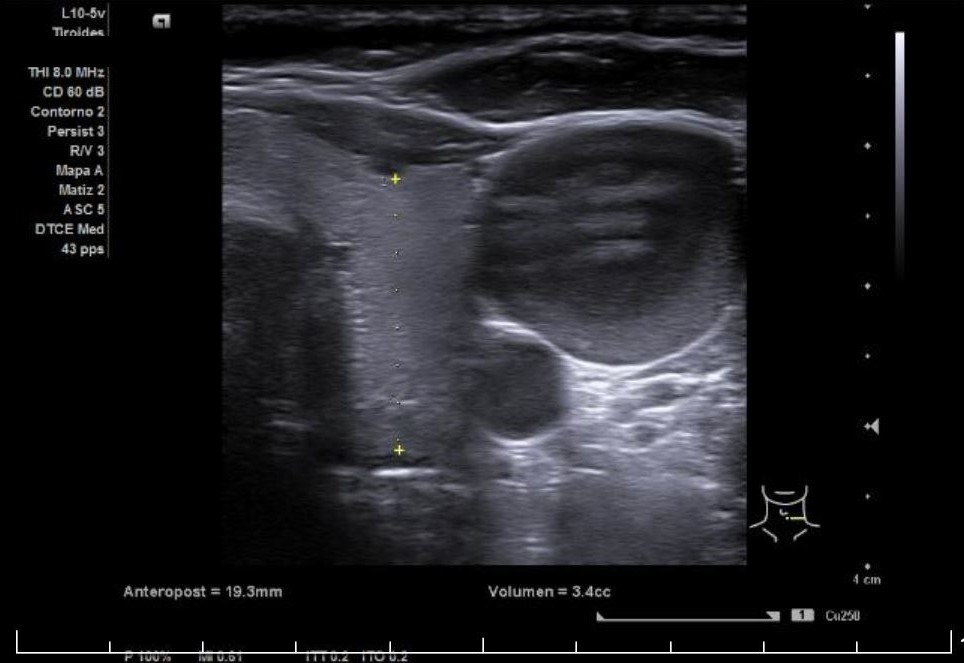

Se aprecia un tiroides de características ecográficas compatibles con tiroiditis, sin cambios respecto a ecografía previa, al igual que la grasa peritiroidea derecha, pero de manera incidental se observa un aumento del calibre fusiforme de la yugular externa derecha con respecto a la izquierda, con flujo vascular reducido.

Ante la sospecha clínica y ecográfica de trombosis o flebectasia yugular se derivó a la paciente a urgencias, donde se realizó una ecografía reglada informada como normal, además de Eco-Doppler de troncos supraórticos también informada como normal.

Flebectasia yugular derecha.